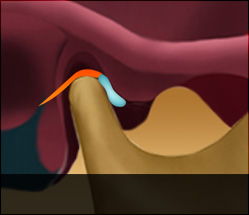

정상디스크 위치

입을 다물고 있는 상태

입을 열고 있는 상태

정상 디스크 위치